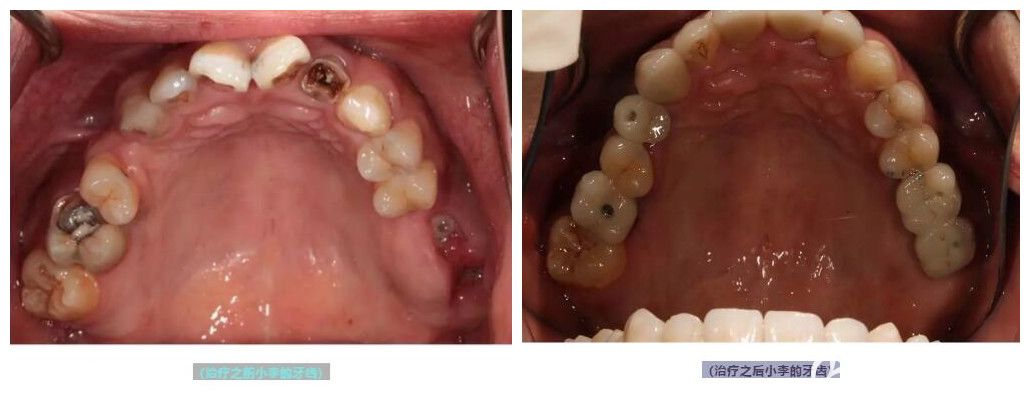

案例:为25岁的小李做即刻种植牙

刚刚二十五岁的小李,牙齿却比五十二岁的人还差,全口多数牙齿龋坏,需要种植。

在面诊过程中被王医生的专业和细致所折服,就选择他做了种植牙手术。

术后评价:做完种植牙已有一年时间,在术后的定期复查中并没有发现问题,我现在也和王医生成了朋友,经常会在微信上聊天,也感谢王医生,让我能够大块朵颐,放肆吃喝。